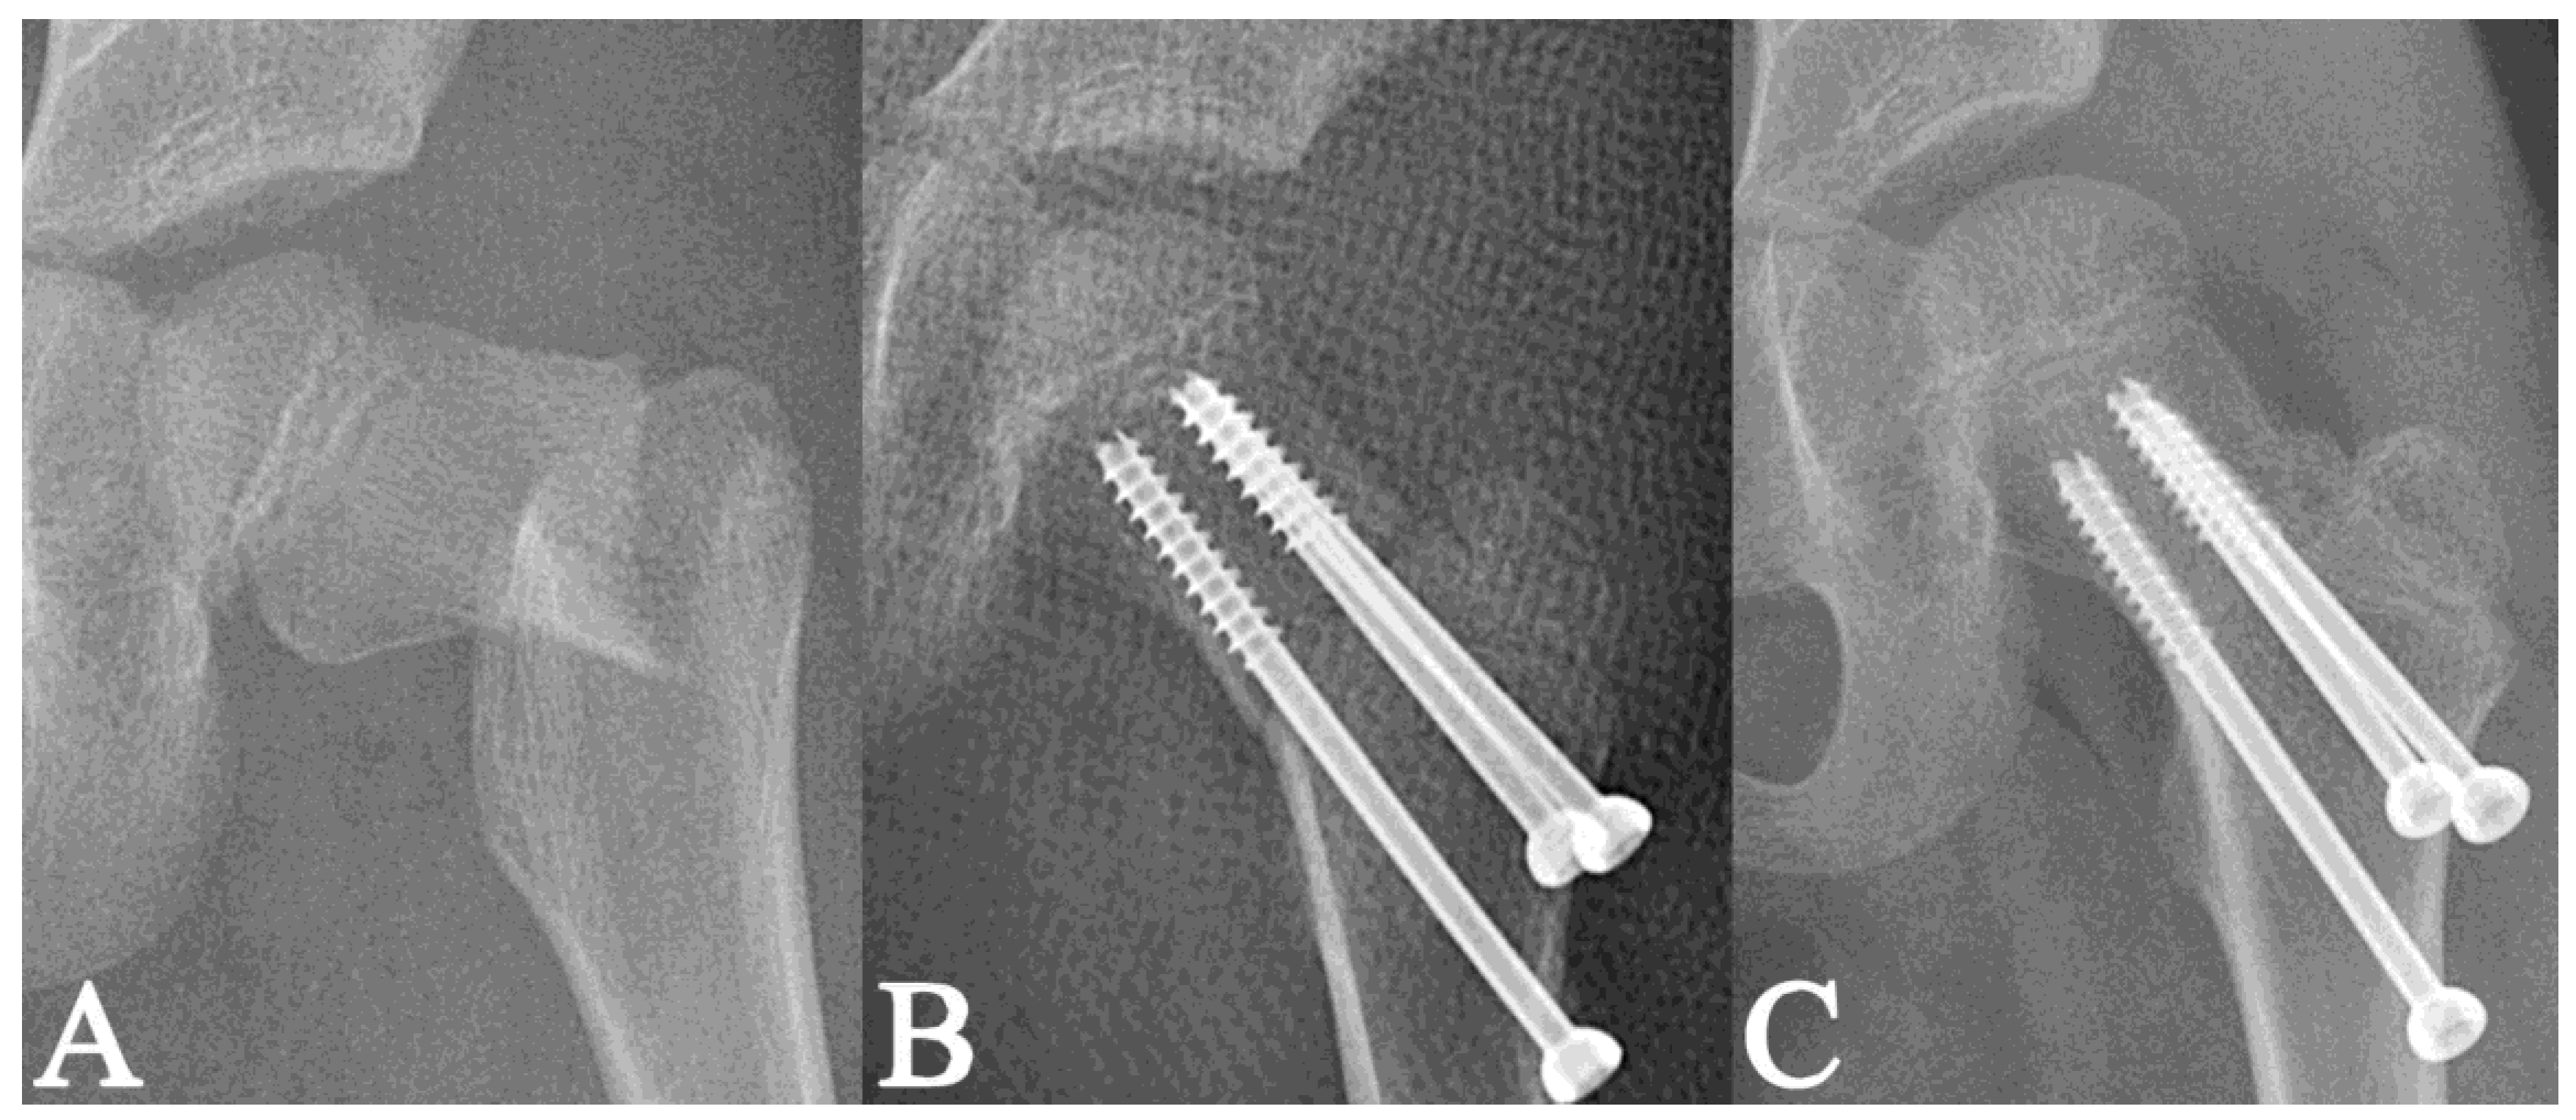

2. Materials and Methods